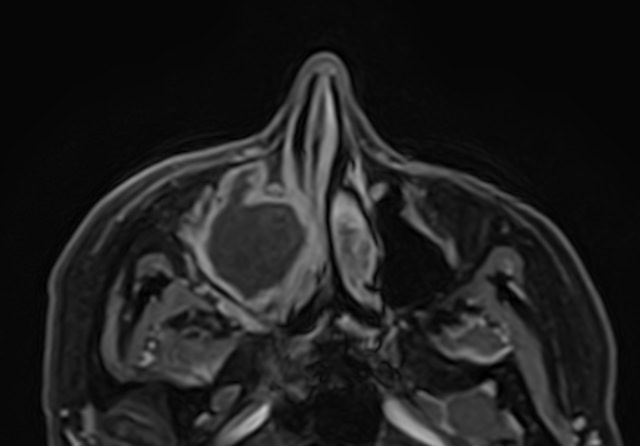

Чаще всего пазухи носа подвержены воспалительным процессам. В зависимости от поражения той или иной пазухи различают гайморит, фронтит, этмоидит, сфеноидит. Реже встречаются доброкачественные и злокачественные опухоли придаточных пазух носа.

МРТ является высокоинформативным способом визуализации данных анатомических областей. Метод позволяет диагностировать различные патологические процессы в области придаточных пазух носа. Кроме высокой информативности МРТ обладает такими преимуществами как достаточная быстрота, безболезненность и безопасность. Метод основан на использовании действия на ткани внешнего магнитного поля, при этом не применяется вредное рентгеновское излучение.

В случае подозрения на развитие опухолевого процесса в обязательном порядке показано введение контрастного вещества для лучшей визуализации патологических изменений в тканях. Степень и характер накопления контрастного препарата в органах и тканях позволяет различать патологические процессы, в том числе диагностировать опухоли на ранних стадиях. Так контрастирование помогает выявлять новообразования размером от 1 мм, что повышает шансы пациента на получение своевременного лечения и выздоровление.